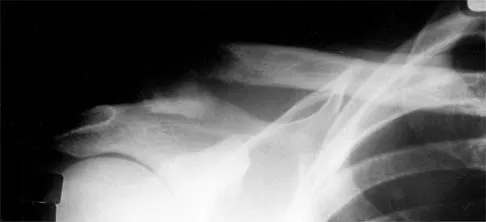

Orthopedic MCQs

Test your knowledge with updated Orthopedic MCQs for 2026. Perfect for board exam preparation, FRCS, and Prometric test practice.